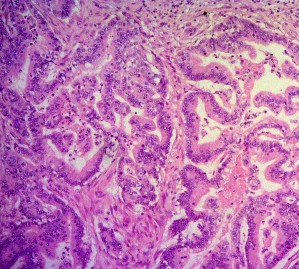

Ảnh 7. Tế bào học: UTBM bóng Vater xâm nhập mạch máu. Mã số ST0449, nhuộm H&E x 100 | Ảnh 8. Tế bào học: UTBM bóng Vater di căn hạch. Mã số ST0449, nhuộm H&E x 100 |